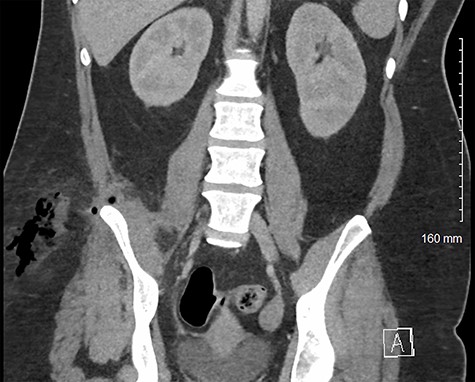

A normally fit and well 33-year-old woman presented to the emergency department with right flank and thigh pain for 3 weeks. She had previously been seen in primary care following 1 week of thigh pain, which was initially attributed to a musculoskeletal cause for which she was advised to take simple analgesia. The patient returned to the emergency department when the pain significantly worsened, and she developed an associated fever. Apart from a high body mass index, she had no other co-morbidities. On examination, she had diffuse erythema and tenderness over her proximal thigh, particularly marked on the medial aspect (Fig. 1). The erythema extended to her ipsilateral iliac crest. There was no palpable fluctuance or crepitus. Pain was exacerbated by movement at the hip joint, but there was no reduction in the range of movement. There was no guarding or tenderness on abdominal examination. At this time, her temperature was 39.3°C. She was tachycardic at 152 beats per minute but was normotensive, with a blood pressure of 111/57 mmHg. Her respiratory rate was 19, and she was saturating at 96% on air. Her white cell count was 19.2 (109/l), and her C-reactive protein was 148 (mg/l). She was scheduled for immediate surgical exploration of the flank and thigh under the plastic surgery team as necrotizing fasciitis could not be excluded. Given the atypical presentation, a prompt computed tomography (CT) scan of the abdomen and pelvis prior to surgical exploration was undertaken. This demonstrated large volume subcutaneous emphysema in the soft tissues of the thigh and flank. This was associated with a fistula tracking superior to the right iliac wing, originating from an appendiceal collection involving the iliacus muscle and the pelvic sidewall (Figs 2 and 3).

Axial CT image of patient at L5 level, demonstrating inflamed perforated appendix adherent to the pelvic sidewall. This also shows an abscess in the subcutaneous fat of the flank/proximal thigh.